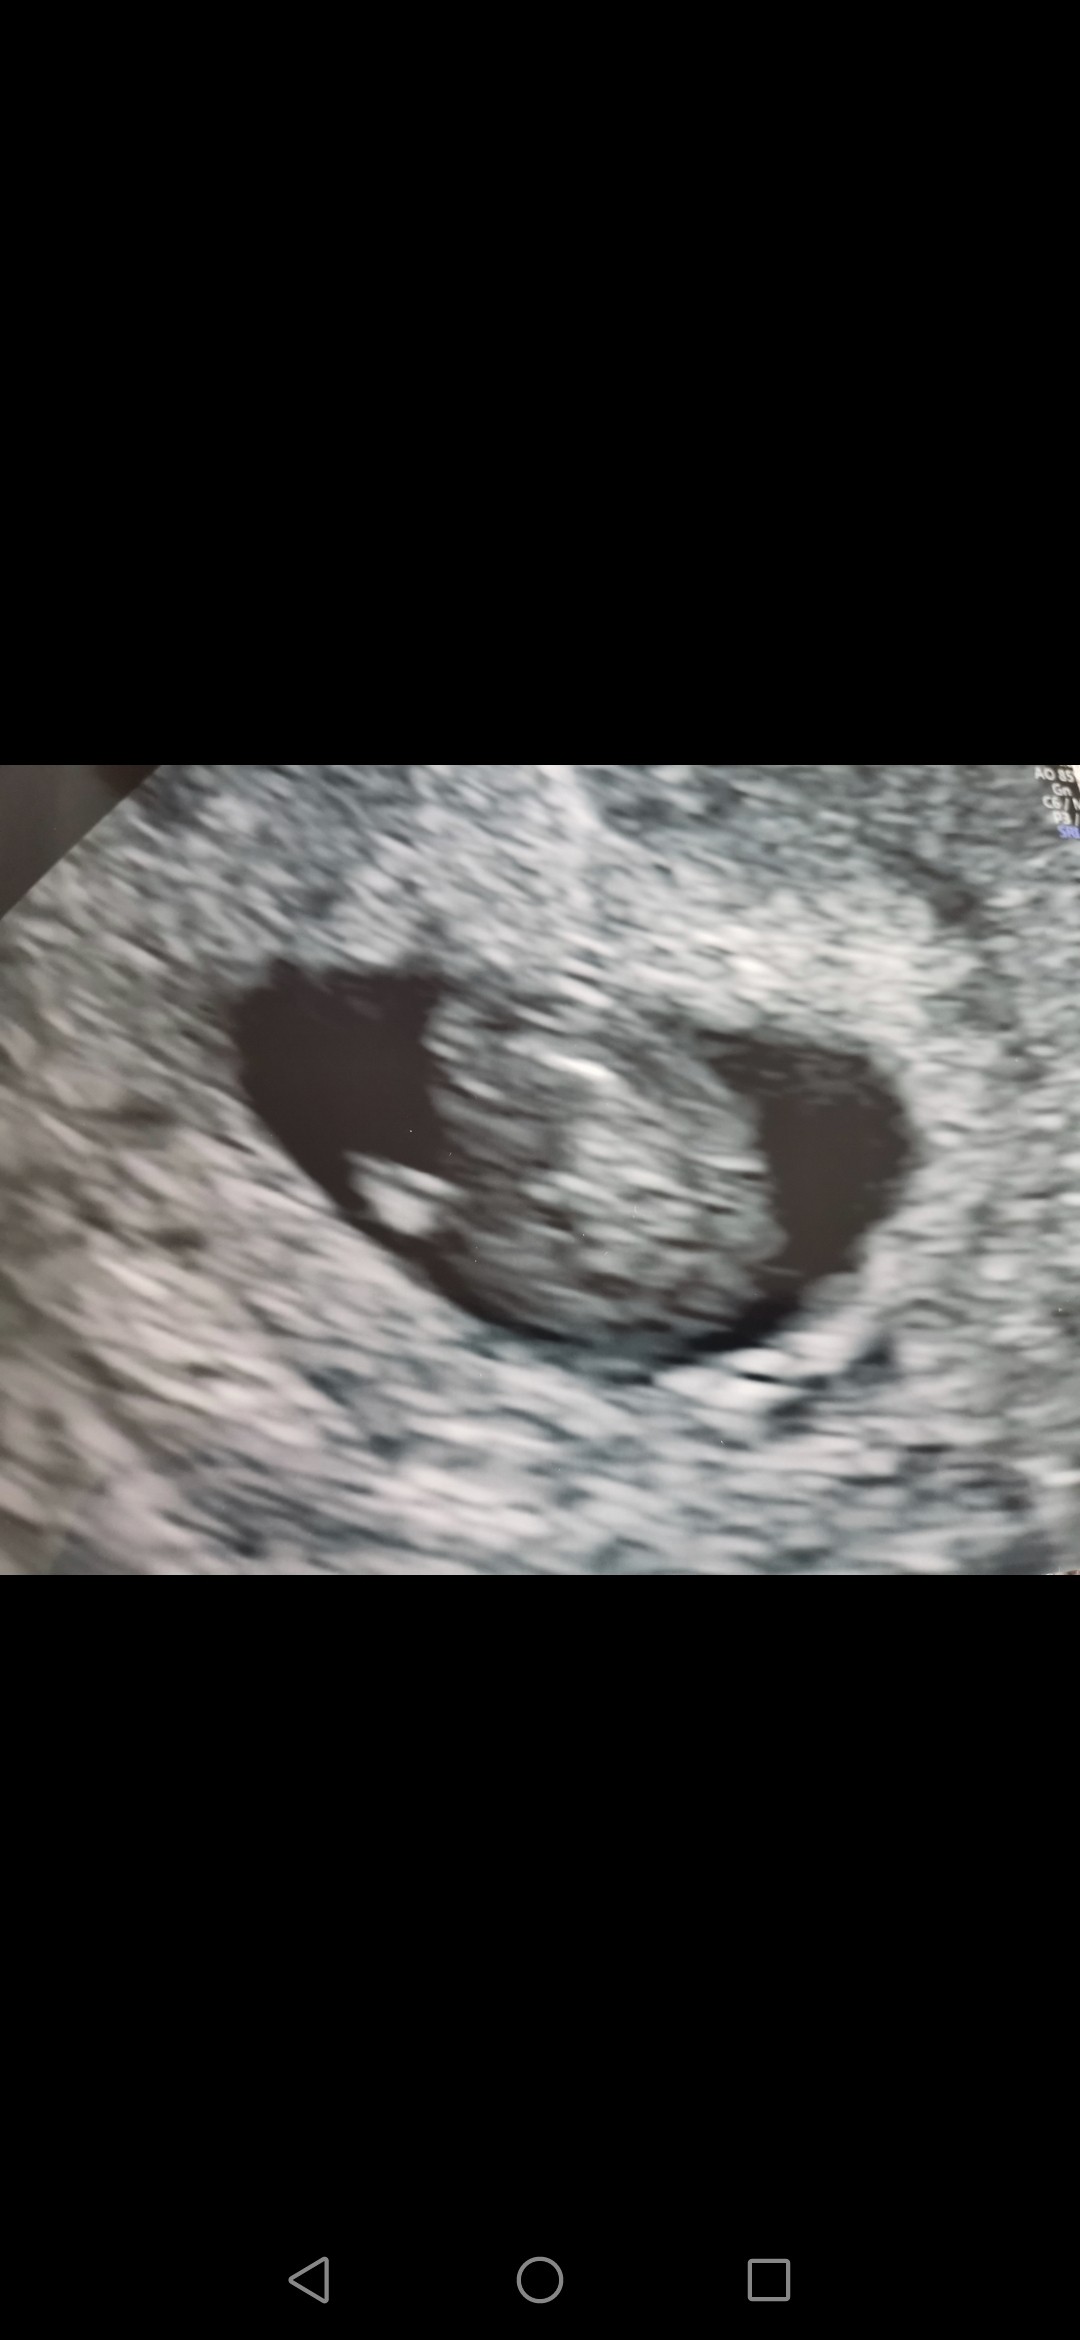

Hej dziewczyny. Ja już po pierwszej wizycie, serduszko bilo bardzo szybko 😍 wg usg i wg OM dzisiaj jest 7+3. Bardzo się cieszę, że wszystko jest w porządku. Także święta będą spokojniejsze. Myślimy poinformować najbliższą rodzinę o tym, że spodziewamy się dziecka właśnie w Święta 😉Wesołych Świąt Wszystkim 😘

Załączniki

• Screenshot_20210403_104047_com.android.gallery3d.jpg

Screenshot_20210403_104047_com.android.gallery3d.jpg

139,8 KB · Wyświetleń: 111